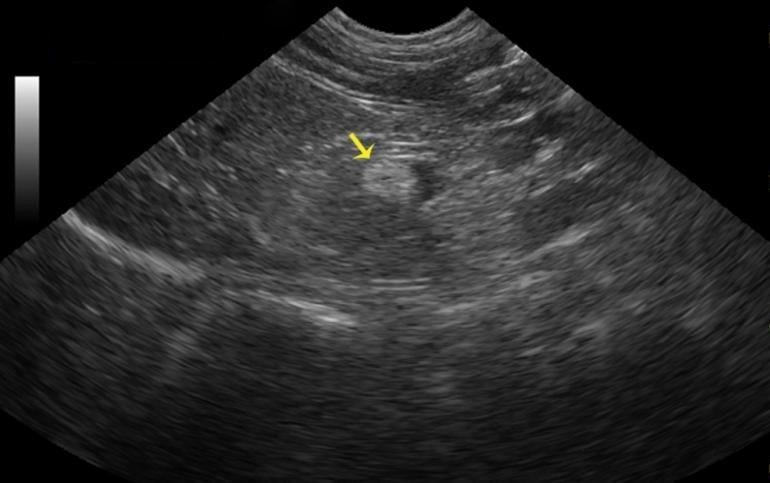

Для диагностирования аденомы надпочечников назначают проведение следующих процедур:

- МРТ, КТ, УЗИ;

- Биохимический анализ крови (проверяется уровень гормонов – кортизола, альдостерона, сахара в крови и т.д.);

- Биопсия (в редких случаях, из-за глубокого забрюшинного расположения возможной опухоли).

Как и при любом заболевании, важным моментом остается соблюдение регулярности врачебных осмотров. Благодаря УЗИ забрюшинного пространства появляется шанс выявить аденому на ранних стадиях, а это позволит предотвратить осложнения.